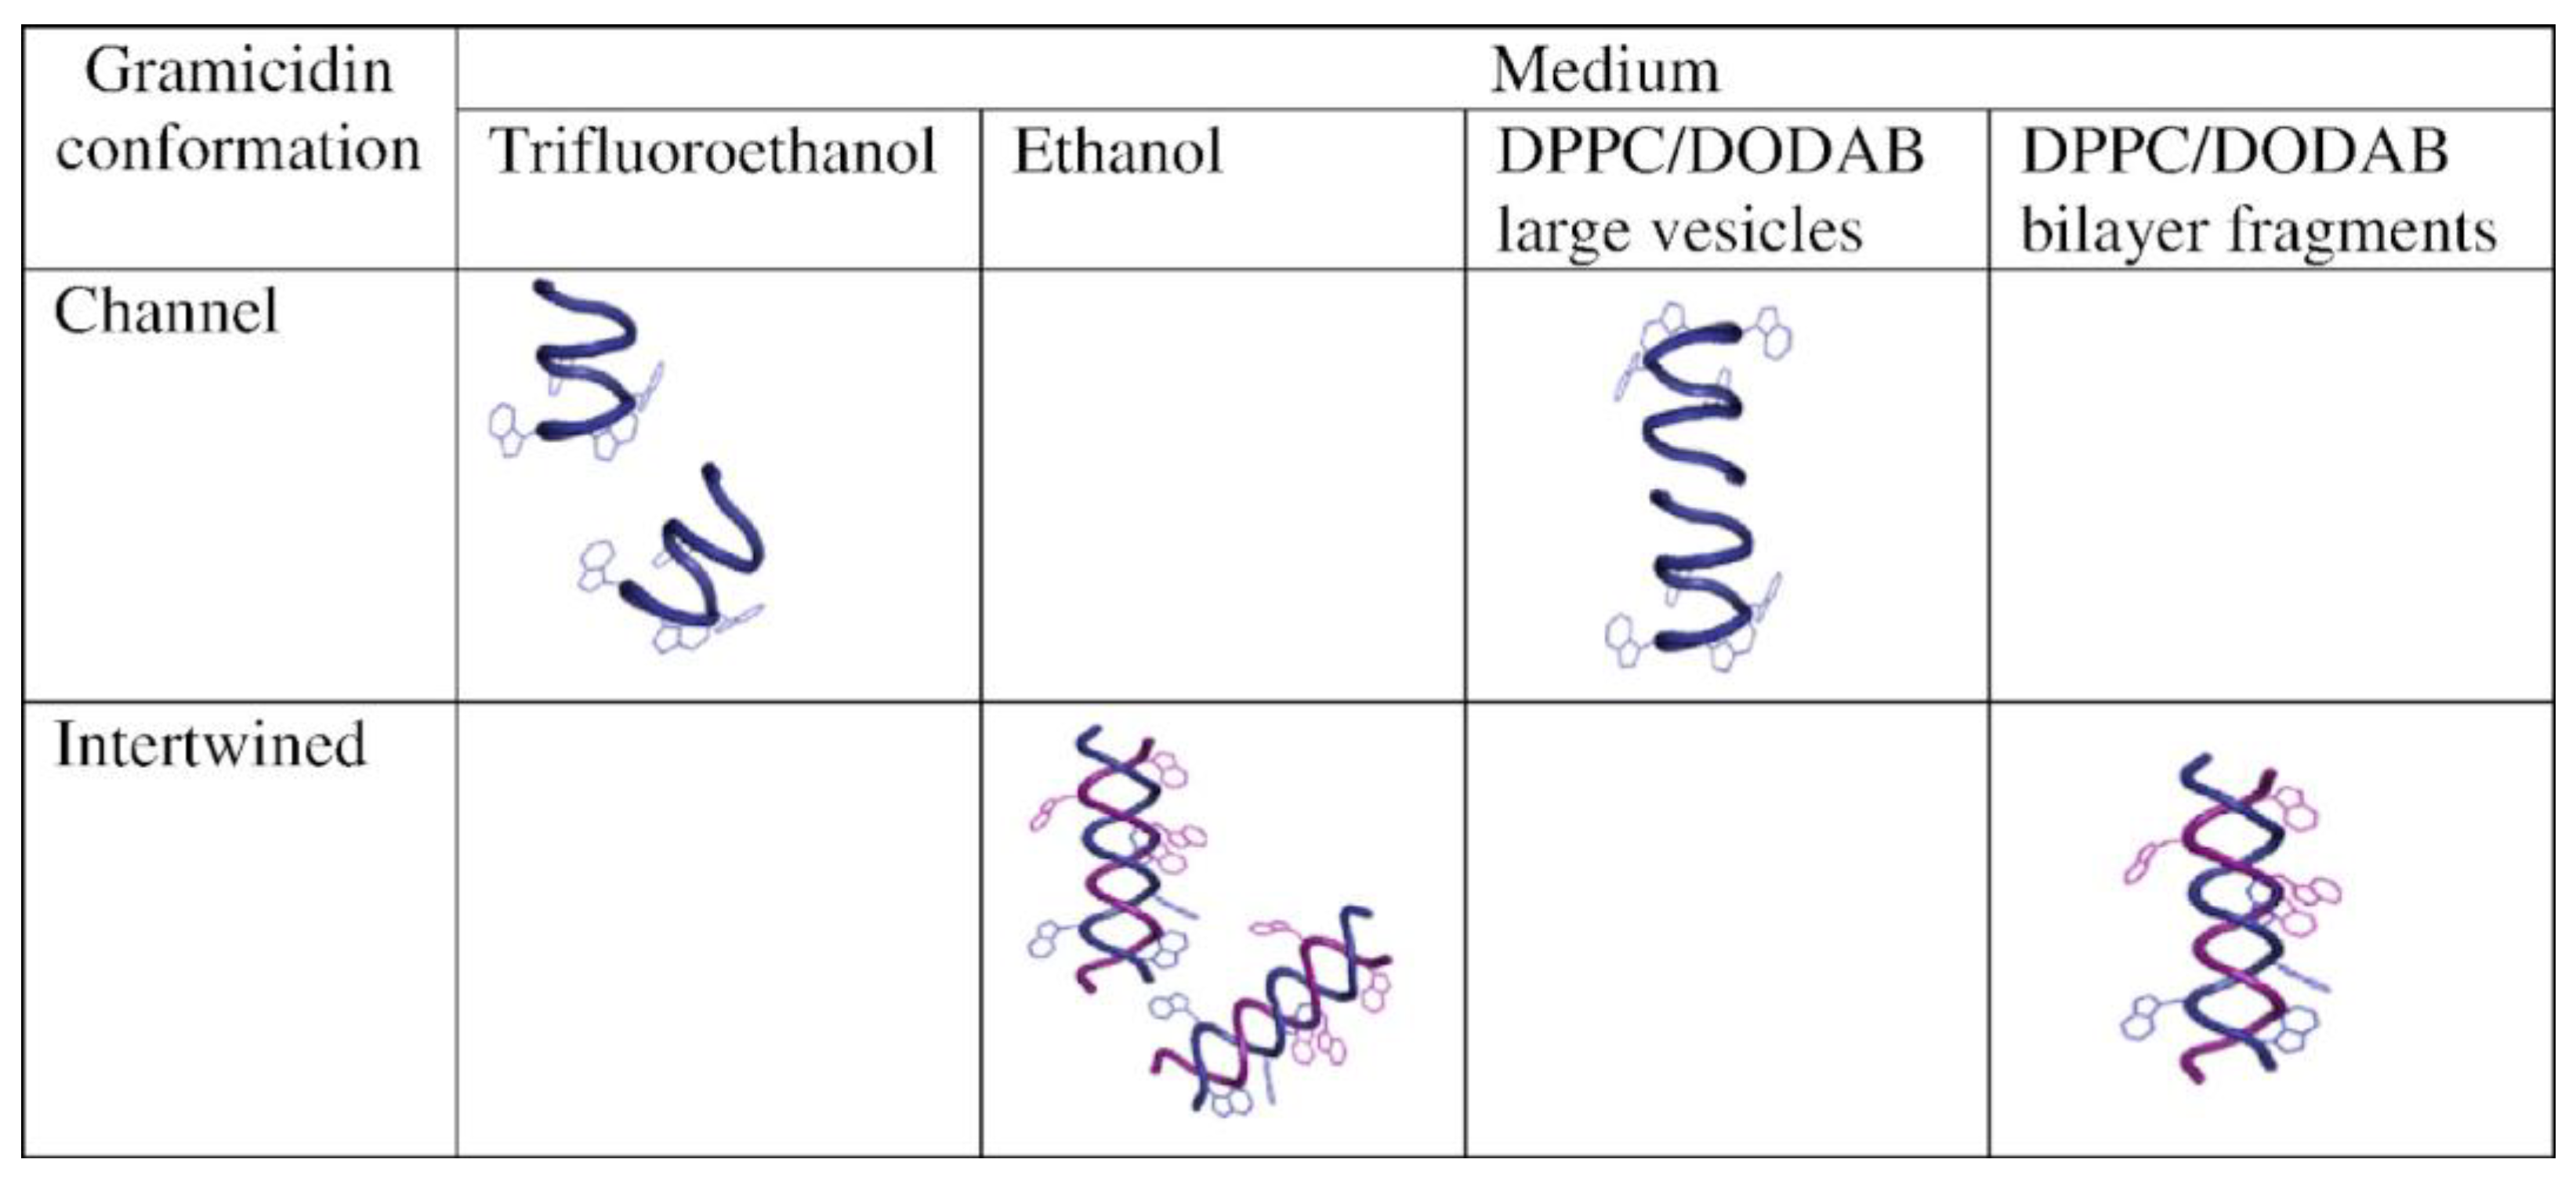

- Carvalho, C.A.; Olivares-Ortega, C.; Soto-Arriaza, M.A.; Carmona-Ribeiro, A.M. Interaction of Gramicidin with DPPC/DODAB Bilayer Fragments. Biochim. Biophys. Acta 2012, 1818, 3064–3071. [Google Scholar] [CrossRef] [PubMed]